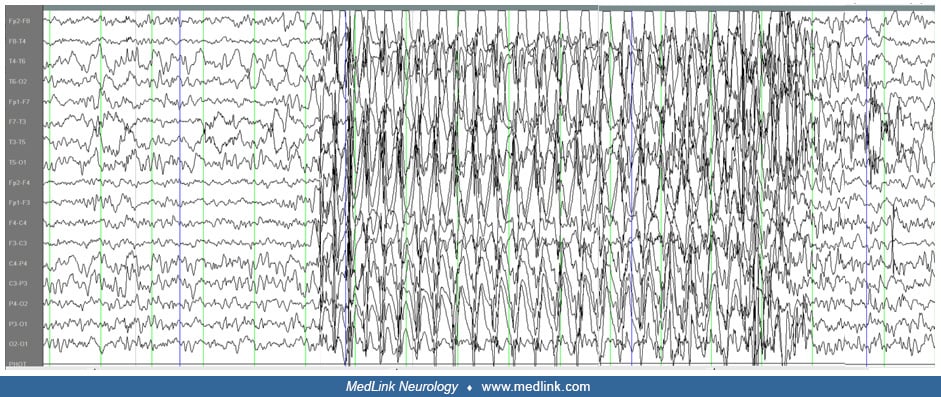

TYPICAL ABSENCE SEIZURE Childhood Absence Epilepsy (CAE) - Petit Mal Epilepsy - Pyknolepsy Childhood Absence Epilepsy | Epilepsy Foundation Frontiers | Absence Seizure Detection Algorithm for Portable EEG Devices | Absence Seizure Eeg